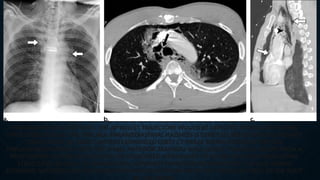

PNEUMOTHORAX FOLLOWING BLUNT CHEST TRAUMA. (A) SUPINE AP CHEST RADIOGRAPH SHOWS DISPLACED LEFT RIB

FRACTURES, SUBCUTANEOUS EMPHYSEMA, AND SUBTLE PNEUMOTHORAX. THERE IS A SIGNIFICANT BASILAR PNEUMOTHORAX

WITH SEVERAL IMAGING CLUES: DEEP SULCUS SIGN, DOUBLE DIAPHRAGM SIGN, AND A WELL-DEFINED LEFT HEART BORDER WITH

FLOATING FAT PAD SIGN. MULTIPLE OPACITIES ARE DEPICTED THROUGHOUT THE LEFT LUNG, COMPATIBLE WITH A COMBINATION

OF CONTUSIONS AND LACERATIONS IN THE SETTING OF TRAUMA. (B) AXIAL CT IMAGE OBTAINED ON THE SAME DAY AS A SHOWS A

LARGE PNEUMOTHORAX; A RADIOGRAPH CAN SIGNIFICANTLY UNDERESTIMATE PNEUMOTHORAX SIZE. TWO INTRAPARENCHYMAL

LACERATIONS ARE DEPICTED IN THE LEFT LOWER LOBE, WITH PNEUMATOCELE AND HEMATOPNEUMATOCELE.